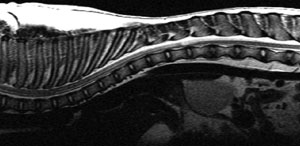

This week there were some great cross-sectional imaging cases. One of the main points was to apply the same principles of interpretation to CT and MR images, regardless of which one you are more used to seeing at your practice for a particular lesion. 9 year old female neutered German Shepherd with … [Read more...]